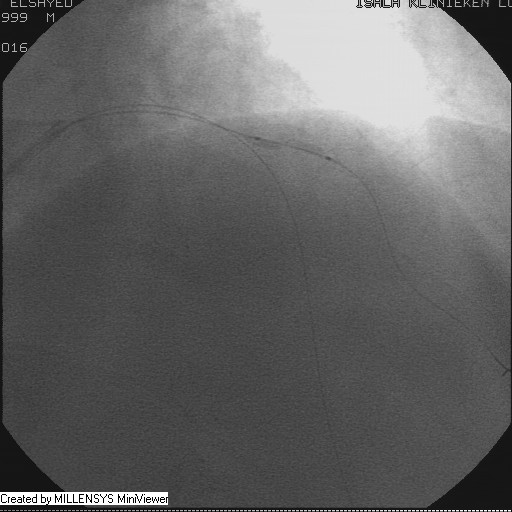

After crossing with the PTCA wire, a minimal flow started to appear in the diagonal branch (Figure 6), then LAD was wired, then a 2x15mm Balloon was used to pre-dilate (Figure 7,8), a big diagonal branch appeared with proximal thrombotic tight lesion (Figure 9), the diagonal angle to LAD was about 90 degree (Figure 10), so provisional stenting done to diagonal from its ostium with 3x20mm PROMUS ELEMENT PLUS DES (Figure 11,12), with good final result (Figures 13&14).

Figure 7

Figure 8